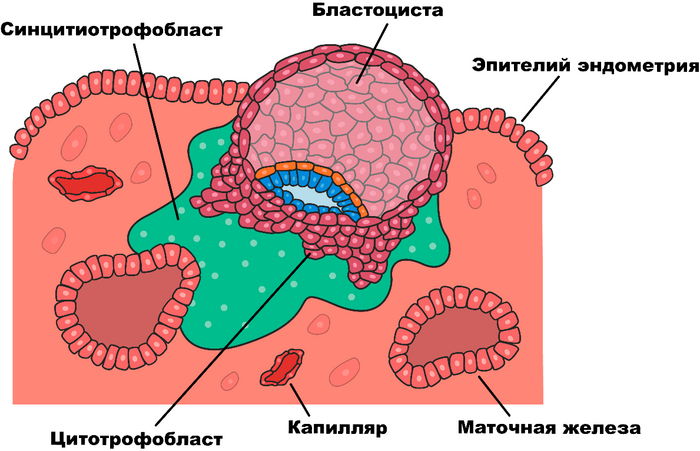

Ну да вернёмся к нашим ретровирусам, собственно, откуда мы знаем об их роли в появлении живорождения у млекопитающих? Всё дело в плаценте, которой обладает каждое живородящее млекопитающее, как сумчатое, так и собственно - плацентарное. Плацента, это довольно любопытное образование, формирующее так называемый синцитий, это когда клетки сливаются между собой в как бы одну большую многоядерную клетку. Плацента выполняет ряд серьёзных функций необходимых для нормального протекания беременности, как то: газообмен, снабжение питательными веществами, выведение продуктов метаболизма плода, секреция ряда гормонов и… плацента умеет подавлять иммунитет матери.

Это требуется для того, что бы организм матери не отторг находящийся внутри него чужеродный объект, в виде будущего чада. Срок беременности у териев гораздо больше, нежели инкубационный период у завропсид и даже однопроходных млекопитающих, ведь нахождение в утробе матери создаёт для развития плода наиболее комфортные условия - температура вокруг всегда одинаковая, кислорода и питательных веществ в достатке, да и ядовитые метаболиты выводятся исправно, а значит можно и не торопится с появлением на свет и спокойно развиваться до приемлемых размеров!

Итак, выделим два основных интересующих нас пункта свойственных плаценте: первое это слившиеся клетки, а второе – подавление иммунитета. Эти свойства удивительно напоминают действие одного из ретровирусных белков – ENV (от английского envelope - оболочка). Конечно же, вирус использует этот белок не для пользы матери и ребёнка, а с целью подавить иммунитет и, заставив клетки слиться, тем самым расширив свои охотничьи угодья и воспользовавшись всеми ресурсы синцития.

В 2000-м году, две группы учёных возглавляемых Джоном Мак-коем из США и Франсуа Малле из Франции, одновременно обнаружили в плаценте человека эндогенный ретровирус, который назвали Human Endogenous Retrovirus-W или HERV-W, белку оболочки вируса было присвоено имя синцитин, так как его функция напрямую связана с образованием синцития в плаценте. Так же обнаружилось, что если отключить ген, отвечающий за производство данного белка, то беременность протекает с патологиями вызванными дисфункцией сосудов. В 2003-м году был открыт ещё один ретровирус участвующий в образовании плаценты - HERV-FRD и его белок, названый синцитином второго типа.

Так же, на примере сумчатых хорошо видна эволюция плаценты, по сути, беременность сумчатых частично напоминает этот процесс у яйце-живородящих завропсид: сначала зародыш начинает своё развитие в яйце внутри организма матери и лишь незадолго до родов вылупляется из яйца и прикрепляется слабой плацентой к эндометрию матки матери и через не очень длительное время происходят роды. Период имплантации зародыша к стенке матки, является самым опасным для жизни зародыша, около 75% неудачных беременностей у плацентарных приходятся именно на него.

Дело в том, что в момент прикрепления зародыша и начала образования плаценты, происходит воспаление стенки матки и наши добрые друзья Т-лимфоциты, спешат на помощь и с шашкой наголо, мчатся уничтожать непрошеного гостя, именно эта реакция вызывает тот самый токсикоз у беременных. Но тут, в дело вступает ретровирусный белок, который заставляет Т-лимфоциты не только не атаковать свежезакрепившийся плод, но и защищать его от чужеродных элементов. Затем, к моменту родов, воспаление возобновляется и происходит отторжение плаценты маткой, и непосредственно - роды. Но вот у сумчатых, плацента практически не влияет на иммунный ответ организма, поэтому основную часть своего развития, их детёныш проводит в яйце. Это подтвердили исследования домового опоссума, принадлежащего к сумчатым млекопитающим, опубликованные в 2000 году профессором биологии из Австралии Линни Селвуд.